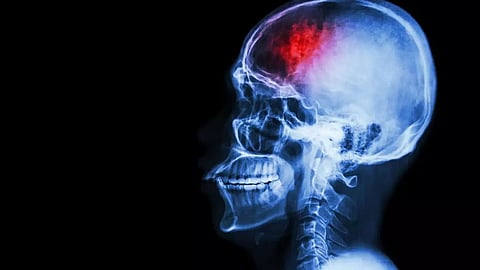

NEW YORK: Making a compelling case for the expected long-term effects on the brain and nervous system by the COVID virus, new research that included scientists of Indian origin and reviewed a century of data showed that COVID-19 is likely to impact the brain in the long run.

The question is to what degree and under what form. Even mild COVID-19 infection may have negative effects on the brain in the long term, according to researchers from the University of Texas Health Science Center at San Antonio (UT Health San Antonio) in the US.

The olfactory bulb connects with the hippocampus, a brain structure primarily responsible for short-term memory, said the article published in 'Alzheimer's & Dementia: The Journal of the Alzheimer's Association'. "The trail of the virus, when it invades the brain, leads almost straight to the hippocampus," de Erausquin said.

That is believed to be one of the sources of the cognitive impairment observed in COVID-19 patients. "We suspect it may also be part of the reason why there will be an accelerated cognitive decline over time in susceptible individuals," de Erausquin said.